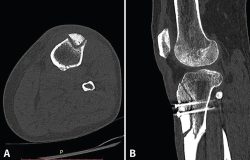

A los 6 meses de la cirugía consulta por dolor de inicio brusco, a la carga, sin antecedente traumático. A la exploración presenta subderrame con dolor difuso que dificulta la exploración. La radiografía (Rx) y la resonancia magnética (RM) (Figura 1) muestran una fractura metafisodiafisaria espiroidea proximal de tibia, no desplazada. Ante estos hallazgos, se inicia magnetoterapia, carga parcial según la tolerancia, inmovilización con ortesis articulada y se suspende el trabajo de tonificación en cadena abierta. En el control realizado a las 2 semanas refiere persistencia del dolor a la carga; se realiza una tomografía axial computarizada (TAC) que informa de una fractura metafisodiafisaria de tibia proximal no desplazada, con un trazo más evidente en la zona posterolateral, en proceso consolidativo intermedio, con inicio del trazo en el túnel tibial. Una segunda TAC, realizada a los 2 meses, muestra la consolidación de la fractura de tibia. Clínicamente, presenta gonalgia difusa y atrofia muscular; tolera la carga con una muleta. Se retira el inmovilizador continuando con la rehabilitación. Actualmente, el paciente está de alta laboral con secuelas (baremo), alta que impugnó y perdió.

Figura 1. A y B: la radiografía muestra una fractura metafisodiafisaria espiroidea proximal tibia, no desplazada; C: en la resonancia magnética se ve la línea de fractura que afecta la cortical posterior de la tibia.